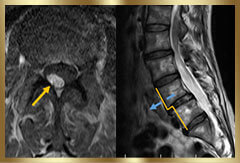

あきらめ半分で手術の専門病院に足を運ぶと…レントゲンとMRIの検査だけで「ヘルニアがあるから手術ね」と告げられてしまったんです。

- レントゲンやMRIではどんな問題があるのか?